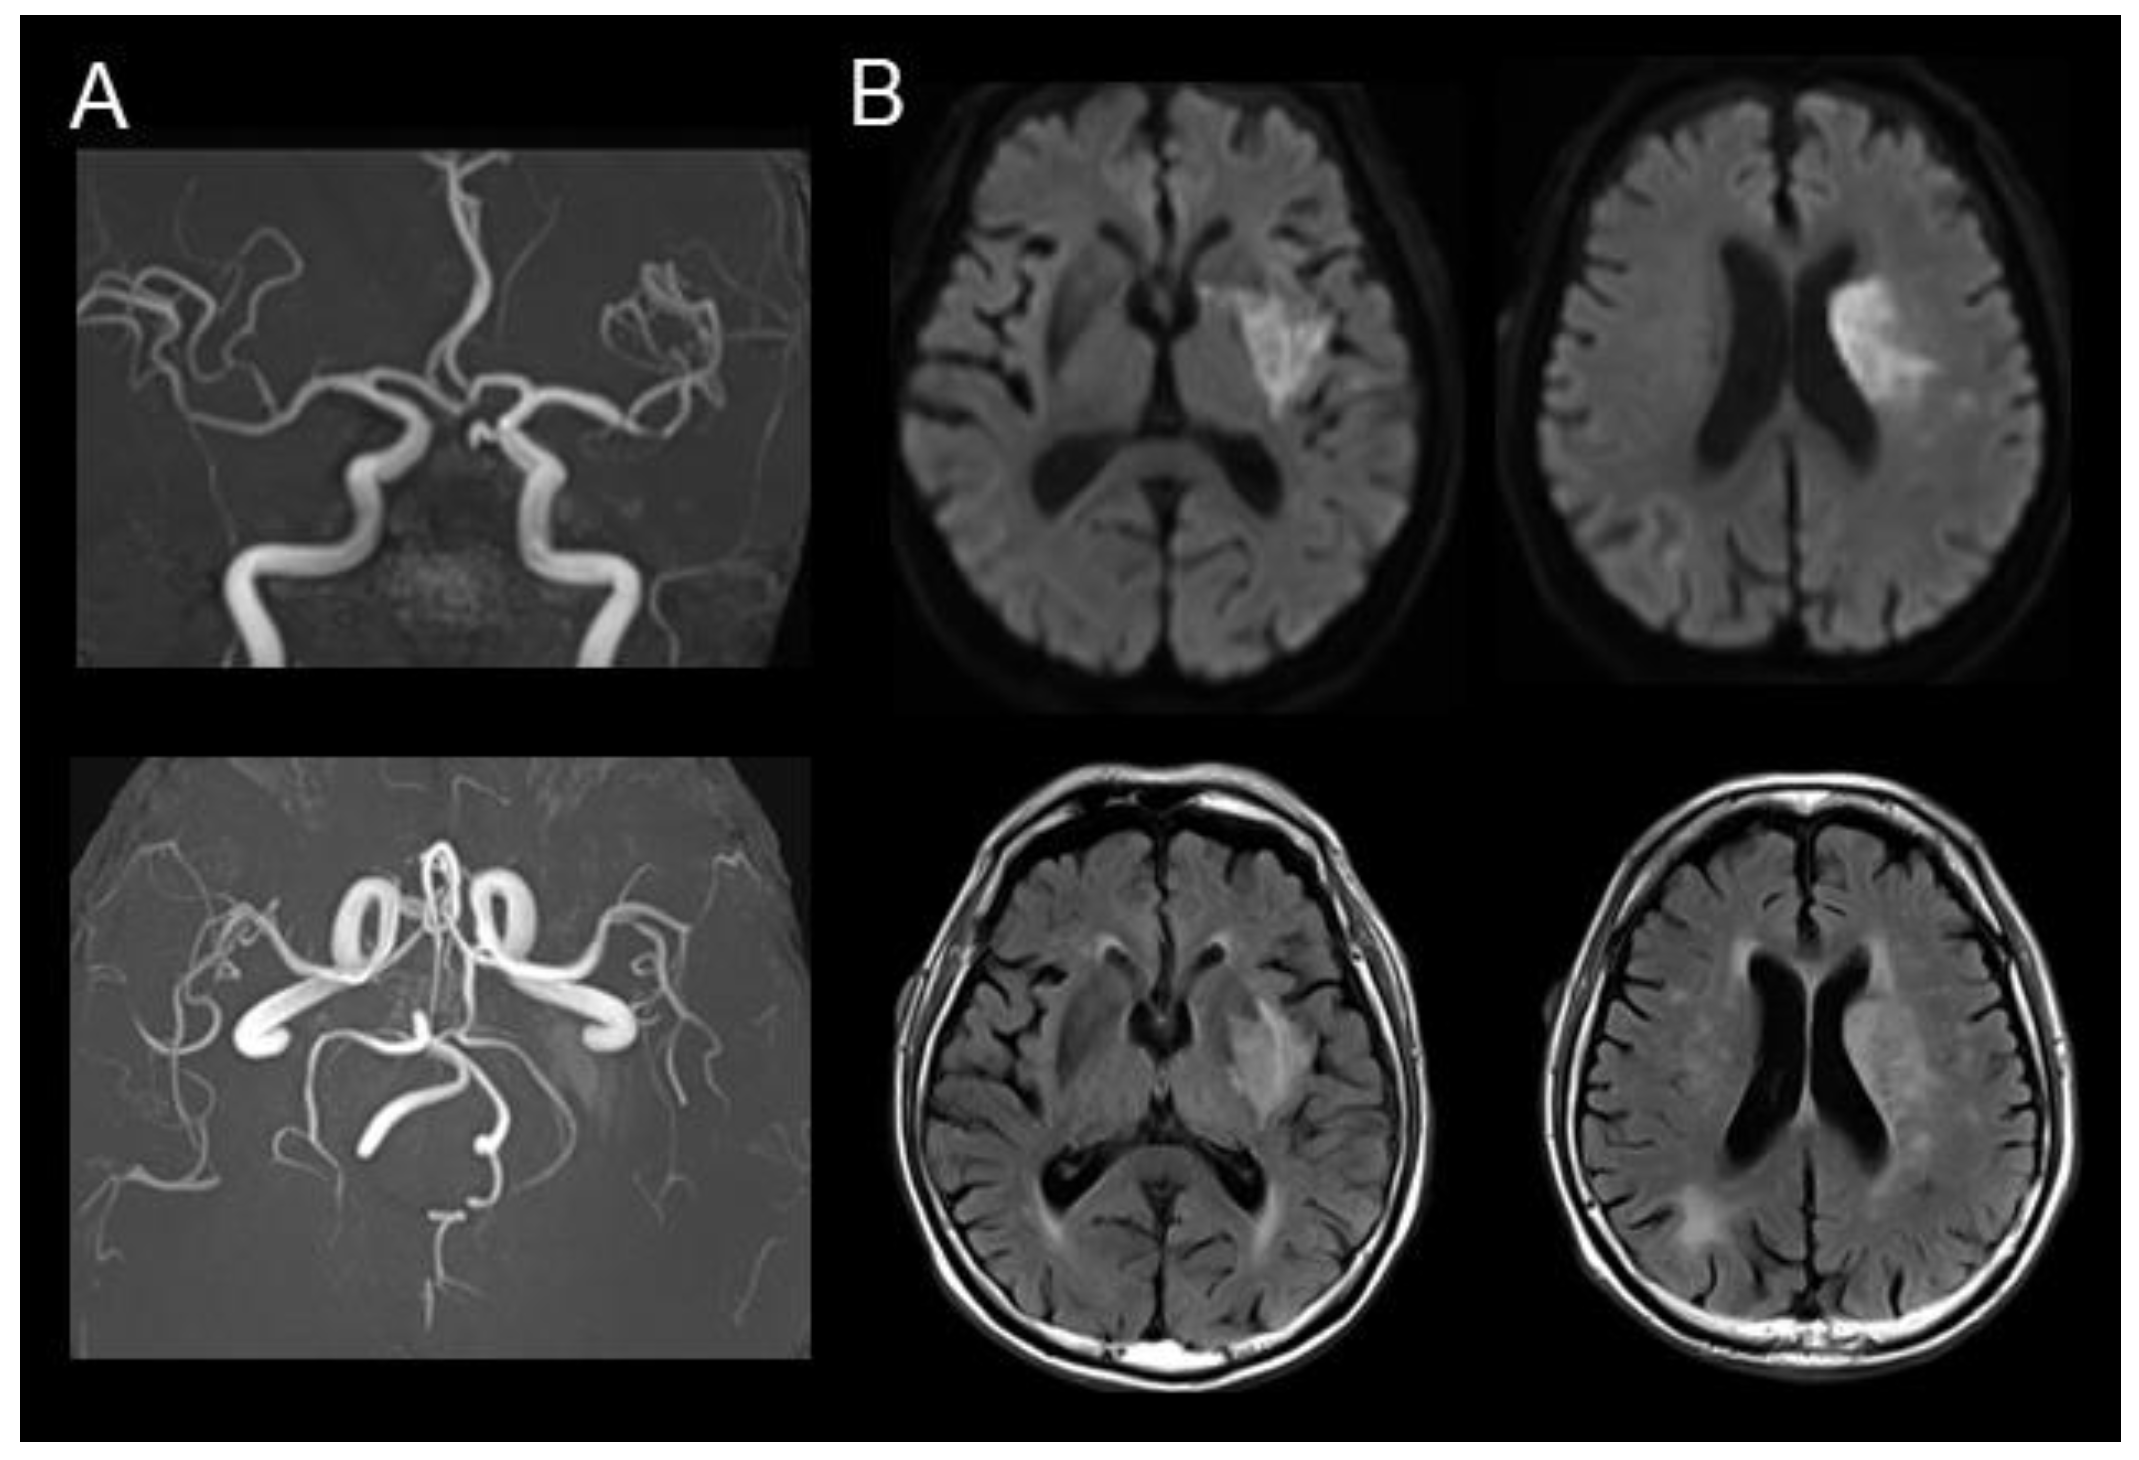

Diffusion MRI Fiber Tractography and Benzodiazepine SPECT Imaging for Assessing Neural Damage to the Language Centers in an Elderly Patient after Successful Reperfusion Therapy

2. Case Presentation